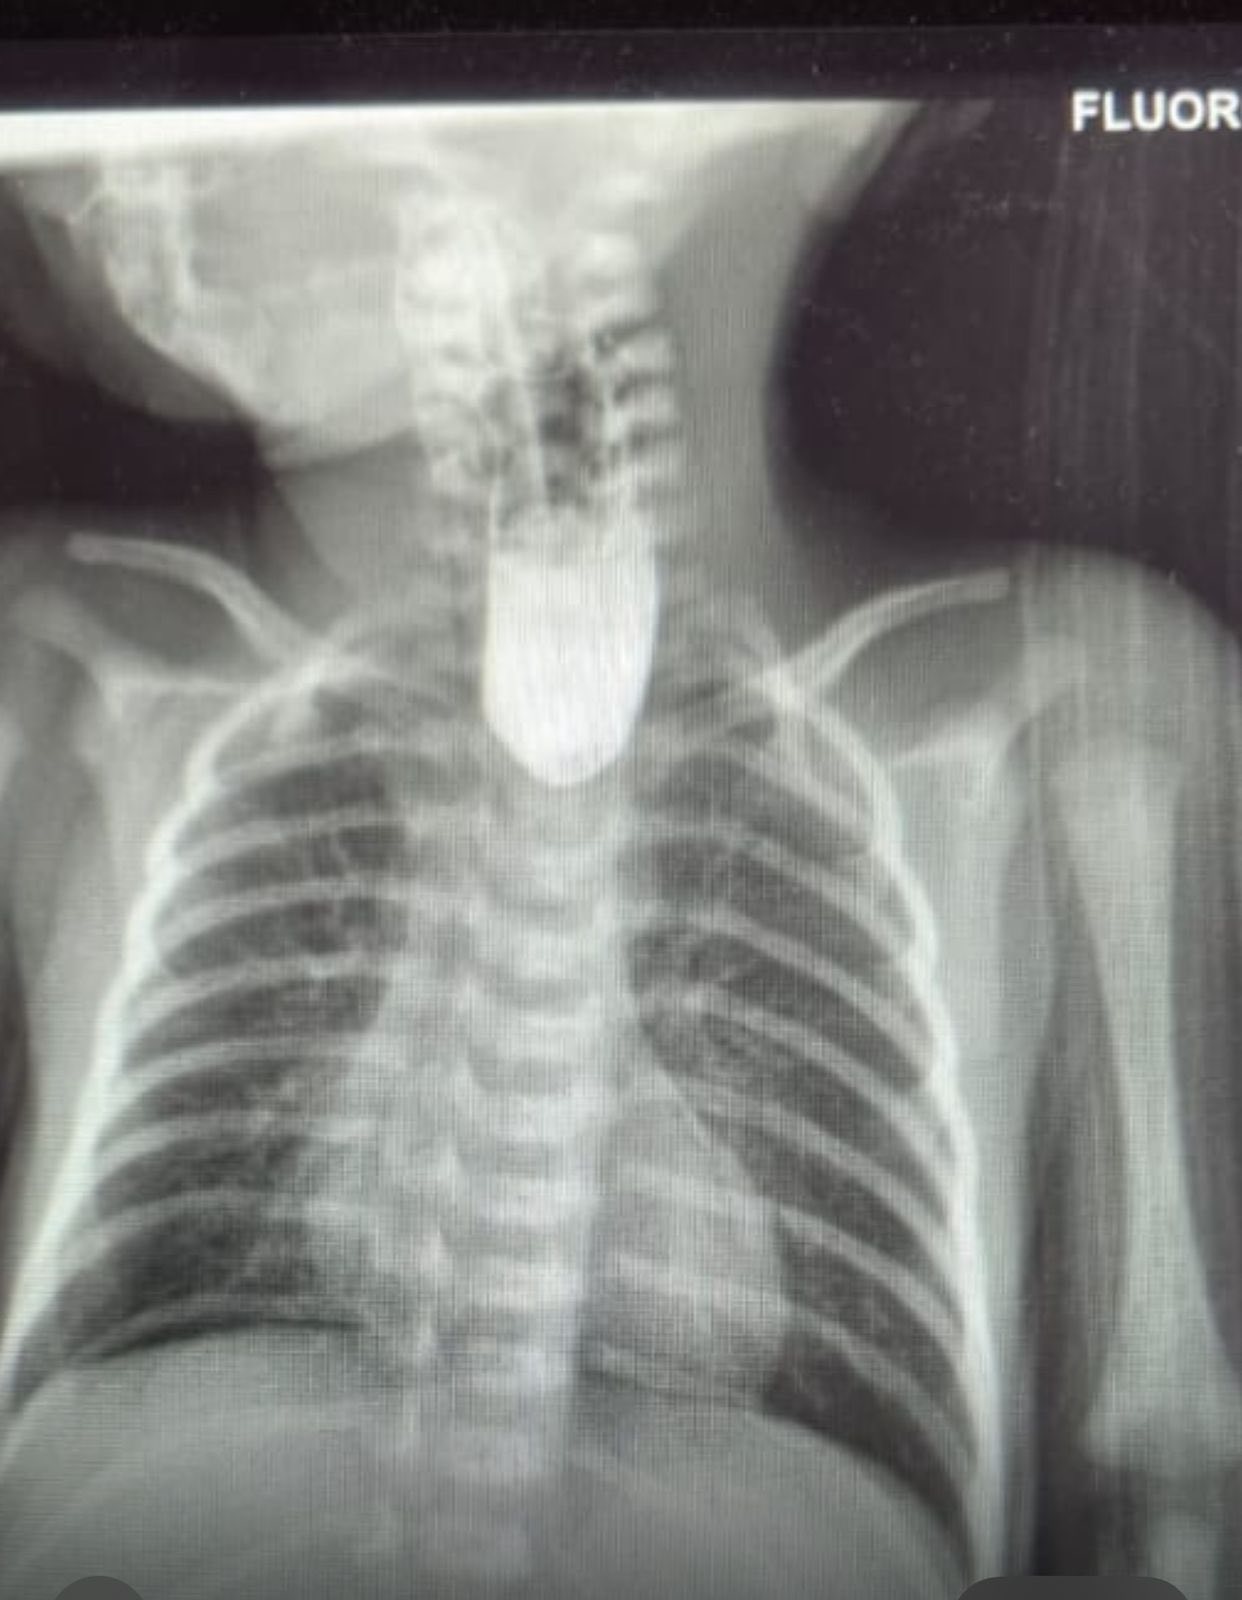

تمكّن الفريق الطبي في قسم جراحة الأطفال وحاضنات الجراحة من إنجاز عملية نوعية ناجحة لطفل خديج ، وُلد مصاباً بتشوّه خلقي نادر في المريء (انقطاع المريء من دون وجود ناسور بين المريء السفلي ومجرى التنفس – النوع الأول من الانسداد المريئي)Isolated esophageal atresia with long gap

أُجريت للطفل العملية الجراحية الأولى بعد ساعات من ولادته لهدف التغذيه المعديه ، تلتها ثلاث عمليات إطالة للمريء esophageal bouginage، ثم العملية النهائية التي تم فيها إعادة توصيل المريء العلوي والسفلي بنجاح.

Delayed 1ry repair

وبعد متابعة دقيقة ورعاية مكثفة استمرت نحو 100 يوم، غادر الطفل المستشفى بصحة جيدة، في إنجاز طبي يعكس مستوى التميز والخبرة المتقدمة في مجال جراحة وتشخيص وعناية حديثي الولادة والخدج في مستشفيات البشير، حيث كان لجهود كادر التمريض في حاضنات الجراحة ومتابعتهم الدقيقة وحسّهم الإنساني العالي الدور الأبرز في نجاح العلاج واستقرار حالة الطفل